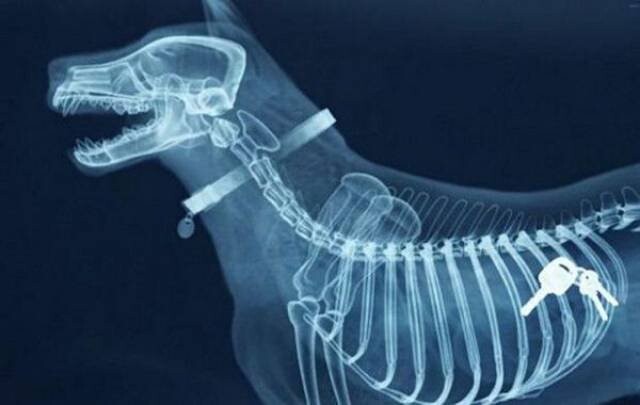

1. Ключи